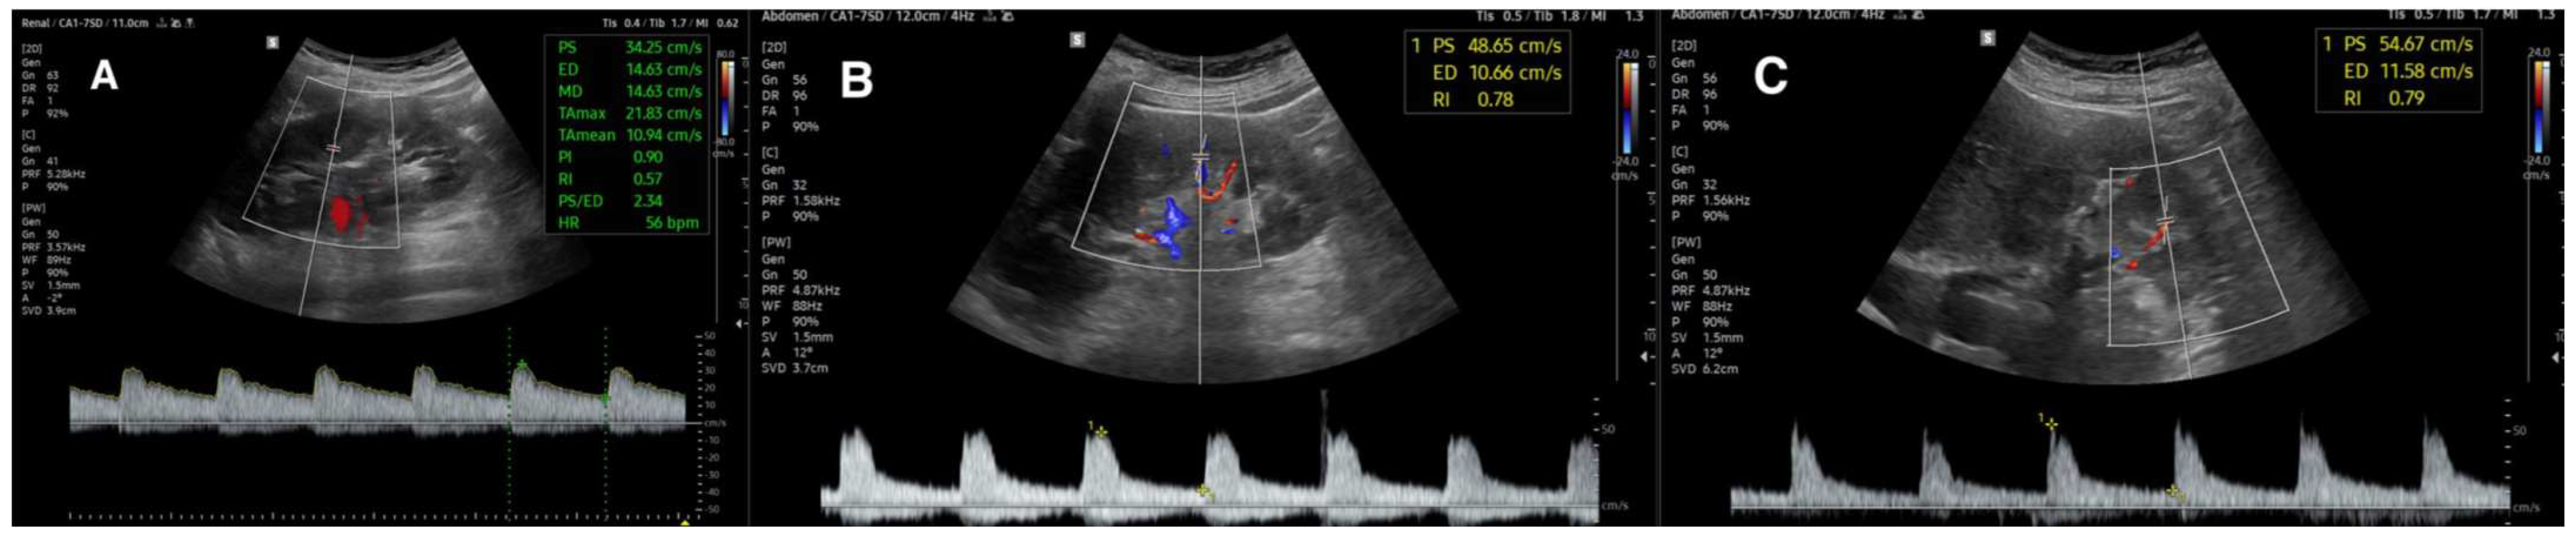

3.2.1. Renal Resistive Index

3.2.3. Acceleration Time and Acceleration Index